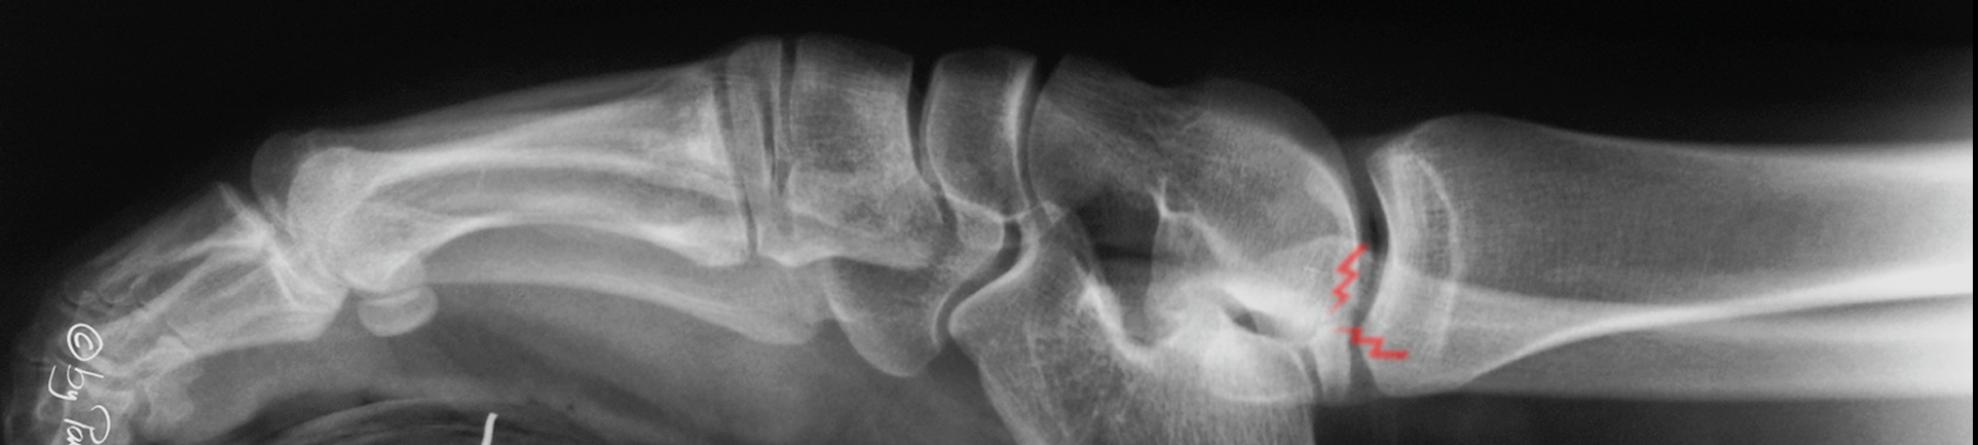

Subtalar Pathology

Post-traumatic ankle Osteoartritis

55 year old engeneer (female) after plane crash

Subtalar osteoarthritis in a patient with multiplanar deformity of the leg

A 58 year old male patient